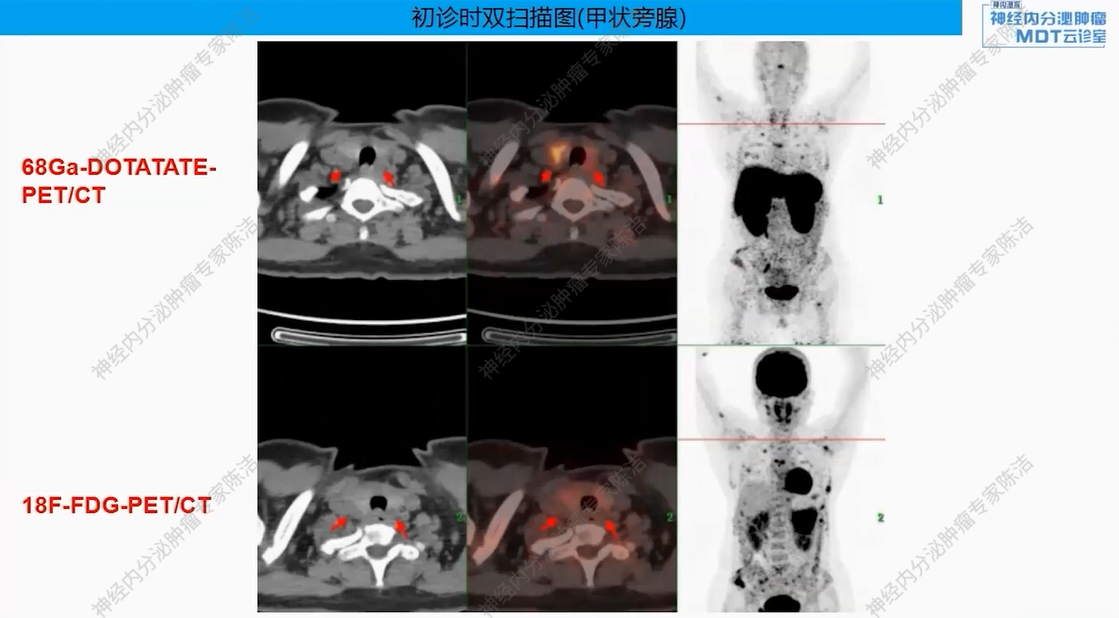

68Ga-DOTANOC-PET-CT提示:胰尾部巨大肿块,DOTANOC摄取阴性;胰体部小结节,DOTANOC摄取阳性。甲状旁腺区多发结节,DOTANOC摄取阳性;垂体区稍增大,DOTANOC摄取阳性。

影像学:垂体MRI提示垂体稍大,最厚9mm,未见明显结节。MIBI甲状旁腺显像提示甲状腺双叶下后方软组织密度影,考虑甲状旁腺瘤,多发骨质改变。

核医学科徐俊彦教授:本病例双扫描PET显像体现了该患者多发肿瘤间异质性。胰尾大病灶(胰岛素瘤)呈SSTR阴性、FDG阳性,这符合约50%胰岛素瘤不表达SSTR的特征。而胰体小病灶呈SSTR阳性、FDG轻度增高。垂体区在SSTR(有生理性摄取)和FDG(无生理性摄取)上均呈阳性,提示垂体瘤可能。骨骼病灶呈SSTR和FDG“双阳性”,高度提示为SSTR阳性的NET转移,但建议对于骨病灶,可对相对表浅的病灶行骨穿以进一步明确骨病灶情况。从最初影像可见髂骨存在明显骨质破坏,甚至骨皮质整体受损,因此骨转移的可能性较大。然而,鉴于该患者同时患有甲状旁腺瘤,甲状旁腺瘤常伴发棕色瘤改变,故目前不能排除甲状旁腺继发的骨改变的可能。

头颈外科王宇教授:在甲状旁腺病灶的处理上,该患者表现出较高的PTH水平(2200+),但术后血钙水平持续正常(约2.4 mmol/L)。怀疑临床检测到的高水平PTH可能是无生物活性的激素片段,而非全长的活性PTH。也可能是患者使用双磷酸盐后高钙血症得以控制。因此,患者虽然有甲状旁腺瘤,但目前血钙正常,可暂不对甲状旁腺进行手术干预。

后续治疗需要明确多发骨质改变的性质,建议对骨病灶进行穿刺活检。此举旨在鉴别其究竟是SSTR阳性的NET骨转移,还是甲状旁腺病变相关的骨病。若证实为SSTR阳性的NET转移,可考虑使用小剂量长效生长抑素类似物进行治疗。若证实为甲旁亢相关骨病,或活检未见肿瘤细胞,则无需使用生长抑素类似物。关于甲状旁腺处理,患者目前无明显血钙升高,可暂不手术,密切随访血钙、PTH变化。对于垂体处理,建议完善垂体薄层动态增强MRI以明确诊断,并评估对周围组织器官压迫情况。